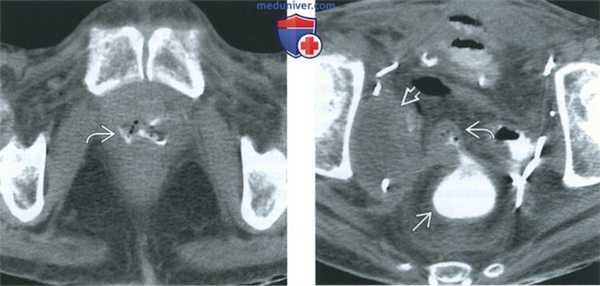

(Слева) При КТ в аксиальной плоскости с контрастным усилением, выполненной с введением контрастного вещества в прямую кишку, в просвете влагалища визуализируется воздух и контрастное вещество, что позволяет заподозрить ректовагинальный свищ. Пациентке незадолго до обследования был проведен курс лучевой терапии в связи с рецидивом опухоли малого таза.

(Справа) При КТ в аксиальной плоскости с контрастным усилением на более высоком уровне, выполненной у той же пациентки, видно, что свищ отходит от передней стенки прямой кишки. Свищ содержит контрастное вещество и небольшое количество воздуха. Отмечается также обширное поражение лимфатических узлов (лимфаденопатия) боковой стенки таза.